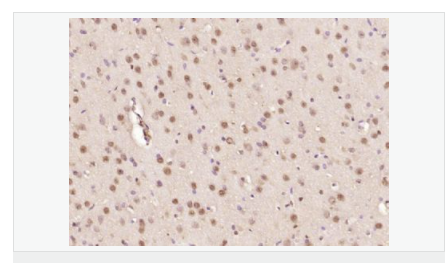

| 產品應用 | ELISA=1:5000-10000 IHC-P=1:100-500 IHC-F=1:100-500 ICC=1:100-500 IF=1:100-500 (石蠟切片需做抗原修復) not yet tested in other applications. optimal dilutions/concentrations should be determined by the end user. |

| 細胞定位 | 細胞核 細胞漿 |

| 產品介紹 | The human ataxin-7 gene, also known as spinocerebellar ataxia 7 or SCA7, maps to chromosome 3p13-p12, has a 2,727-bp open reading frame, and encodes a 892 amino acid protein containing a nuclear localization signal and a polyglutamine tract (1,2). SCA7 is an autosomal dominant neurodegenerative disorder characterized by ataxia and selective neuronal cell loss caused by the expansion of a translated CAG repeat encoding a polyglutamine tract in ataxin-7, which is the SCA7 gene product (3,4). Ataxin-7 is expressed within neurons both affected and unaffected in SCA7 pathology with subcellular localization being variable depending upon the neuronal subtype (5). Polyglutamine expanded in ataxin-7 may carry out its pathogenic effects in the nucleus by altering the matrix-associated nuclear structure and/or by disrupting nucleolar function (6). Function: Ataxin 7 is a protein of unknown function. It may be the human orthologue of the yeast SAGA SGF73 subunit and a subunit of the human TFTC-like transcriptional complexes. Spinocerebellar ataxia 7 (one of a group of hereditary neurodegenrative diseases) is caused by an expanded trinucleotide repeat in the gene encoding ataxin 7. Ataxin 7 is typically located in the cytoplasm and on the nuclear membrane of normal brain neurons. In cells where there is a mutation of the SCA7 gene, ataxin 7 accumulates in intranuclear inclusions and can result in cell death. Subunit: Component of the STAGA transcription coactivator-HAT complex, at least composed of SUPT3H, GCN5L2, TAF5L, TAF6L, SUPT7L, TADA3L, TAD1L, TAF10, TAF12, TRRAP, TAF9 and ATXN7. The STAGA core complex is associated with a subcomplex required for histone deubiquitination composed of ATXN7L3, ENY2 and USP22. Interacts with SORBS1, PSMC1 and CRX. Interacts with TRRAP, GCN5L2 and TAF10. Interacts with alpha tubulin. Subcellular Location: Cytoplasmic (isoform b) and Nuclear (isoform a) Tissue Specificity: Isoform a and isoform b are expressed in CNS, but isoform a is expressed predominantly in the peripherical tissues. Isoform b is also highly expressed in the frontal lobe, skeletal muscle and spinal cord and is expressed at a lower level in the lung, lymphoblast and intestine. Post-translational modifications: Proteolytically cleaved. The cleavage may be involved in SCA7 degeneration: the isoform fragments may exert distinct toxic influences that could contribute to selective neurodegeneration. Sumoylation decreases the aggregation propensity and cellular toxicity of forms with an expanded poly-Gln region but has no effect on subcellular location or interaction with components of the STAGA complex. DISEASE: Defects in ATXN7 are the cause of spinocerebellar ataxia type 7 (SCA7) [MIM:164500]; also known as olivopontocerebellar atrophy III (OPCA III or OPCA3) or olivopontocerebellar atrophy with retinal degeneration. Spinocerebellar ataxia is a clinically and genetically heterogeneous group of cerebellar disorders. Patients show progressive incoordination of gait and often poor coordination of hands, speech and eye movements, due to degeneration of the cerebellum with variable involvement of the brainstem and spinal cord. SCA7 belongs to the autosomal dominant cerebellar ataxias type II (ADCA II) which are characterized by cerebellar ataxia with retinal degeneration and pigmentary macular dystrophy. Similarity: Belongs to the ataxin-7 family. Contains 1 SCA7 domain. SWISS: O15265 Gene ID: 6314 Database links: Entrez Gene: 6314 Human Entrez Gene: 246103 Mouse Omim: 164500 Human Omim: 607640 Human SwissProt: O15265 Human SwissProt: Q8R4I1 Mouse Unigene: 476595 Human Important Note: This product as supplied is intended for research use only, not for use in human, therapeutic or diagnostic applications. |